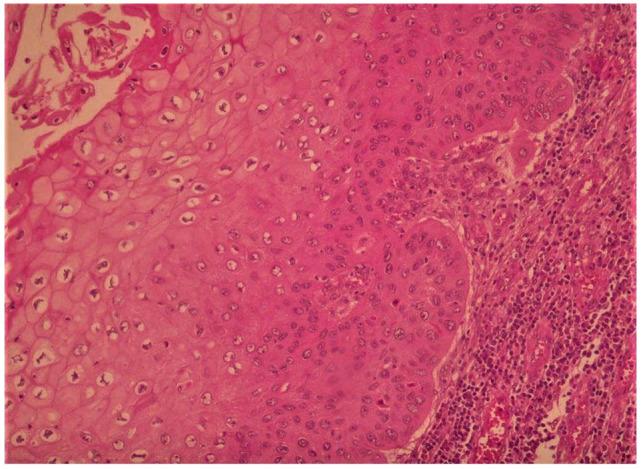

Warty squamous cell carcinoma (WSCC), is a rare variant of squamous cell carcinoma that occurs mostly in younger women, but can occur in old women. It is due to human papillomavirus (HPV) infection. This rare entity has been described in several organs such as vulva, cervix, and penis. To the best of our knowledge WSCC of vagina associated with the third-degree of uterine prolapse has never been reported in the literature. We present an exceptional case of WSCC of vagina occurred in a 77-year-old woman with long disease duration. The physical exam found a large ulcer-budding lesion of the middle and lower third of the vagina that depends on the left vaginal wall. The full work-up concluded to stage IVA of FIGO classification, due to the bladder involvement. The patient underwent a hysterectomy, bilateral salpingo-oophorectomy, bilateral pelvic node dissection, left partial cystectomy with left ureteral reimplantation and total vaginectomy, followed by adjuvant radiotherapy. The patient had no recurrence during 8 years of regular follow-up. WSCC can express locally aggressive behavior, such we reported; despite it appears to be less aggressive than the typical well-differentiated squamous cell carcinoma. That leads to individualize WSCC from other verruciform neoplasms.